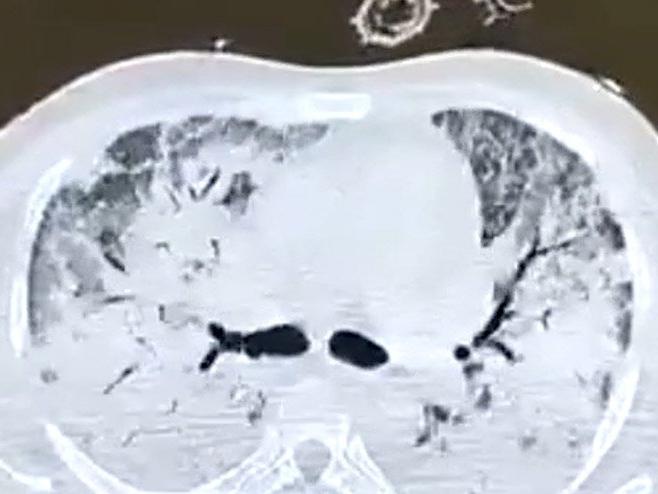

"COVID-19, viral enfeksiyondur" hatırlatması yapan Koca, "Akciğerlerde zatürre dediğimiz şiddetli iltihaplanma olur. İltihaplanma kana yeteri kadar oksijen taşınmasını ve karbondioksitin atılmasını önler. Bu sebeple nefes almak çok güçleşir" bilgisini verdi.